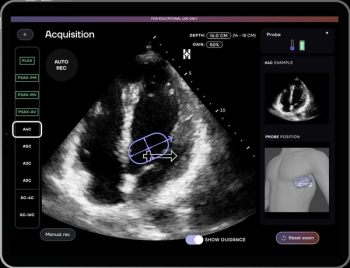

Cardiac CT angiography may provide insights on common post-op complications of left atrial appendage closure, ranging from peri-device leaks to device-related thrombus, according to research presented at the American Roentgen Ray Society (ARRS) conference.